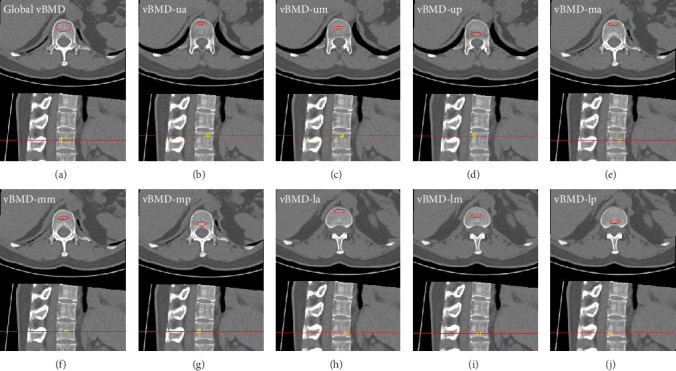

目的:应用定量计算机断层扫描(QCT)探讨2型糖尿病(T2DM)患者椎体压缩性骨折的部位特异性体积骨密度(vBMD)分布,分析其发生机制。材料与方法:304名无T2DM的绝经后妇女和274名有T2DM的绝经后妇女进行QCT扫描,全部分为三个年龄亚组。根据与人体对应的位置将L1椎体划分为9个区域。结果:无论是T2DM还是非T2DM,各年龄组L1椎体从腹侧到背侧,后三分之一区最高,L1椎体从头到脚,中三分之一区最高(p < 0.05)。50 ~ 59岁年龄组T2DM整体及大部分分区vbmd均高于非T2DM, 60 ~ 59岁年龄组vBMD-mp高于60 ~ 59岁年龄组,70 ~ 80岁年龄组vBMD-mm高于非T2DM (p < 0.05)。T2DM患者的vBMDs高于非T2DM患者,且随着年龄的增长差异减小,尤其是L1椎体的上三分之一和下三分之一。结论:椎体压缩性骨折及T2DM与vBMD的混淆可能都是由vBMD分布不均匀引起的。T2DM合并椎体压缩性骨折的高风险可能与全身性和局部特异性vBMD的不同损失率有关,而与vBMD本身无关。

Aims: To explore the distribution of site-specific volumetric bone mineral density (vBMD) and analyze the mechanism of vertebral compression fractures with type 2 diabetes mellitus (T2DM) subjects using quantitative computed tomography (QCT). Materials and Methods: 304 postmenopausal women without T2DM and 274 postmenopausal women with T2DM underwent QCT scan, and all divided into three age subgroups. L1 vertebra was segmented into nine zones based on the corresponding position to the human body. Results: Whether in the T2DM or non-T2DM of each age group, from the ventral to the dorsal side of L1 vertebra, the posterior third zones were the highest, and from the head to the foot of L1 vertebra, the middle third zones were the highest (p < 0.05). Global and most zonal vBMDs of T2DM were higher than those of non-T2DM in the age group of 50-59 years old, vBMD-mp of T2DM was higher in the age group of 60-59 years old, and vBMD-mm of T2DM was higher in the age group of 70-80 years old (p < 0.05). Zonal vBMDs in T2DM were higher than non-T2DM and the difference decreases with age especially in the upper third of L1 vertebra and the lower third of L1 vertebra. Conclusions: Vertebral compression fractures and the confusion between T2DM and vBMD may be all caused by the heterogeneous distribution of vBMDs. The higher risk of T2DM with vertebral compression fractures may be associated with the different loss rate of global and site-specific vBMD, independent of vBMD itself.